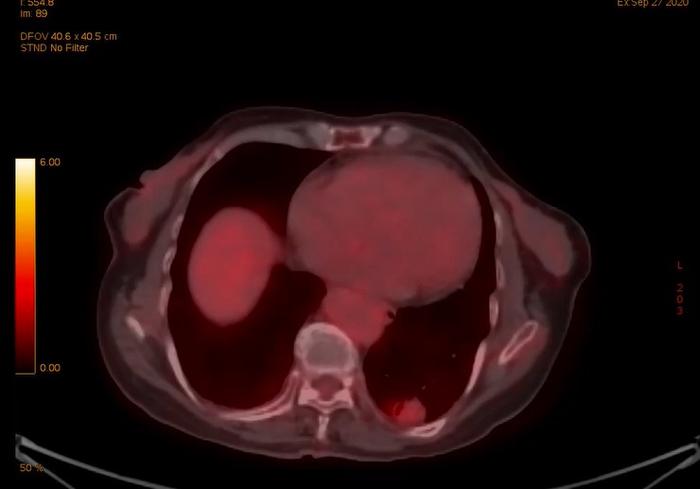

上图是今年住院后左下肺癌的PET,可见结节的代谢稍增高,看起来局部发红一些。

上图是今年住院后左上肺结节的PET,可见结节的代谢正常,看起来与周围组织颜色一样,PET 考虑这个结节是慢性炎症。